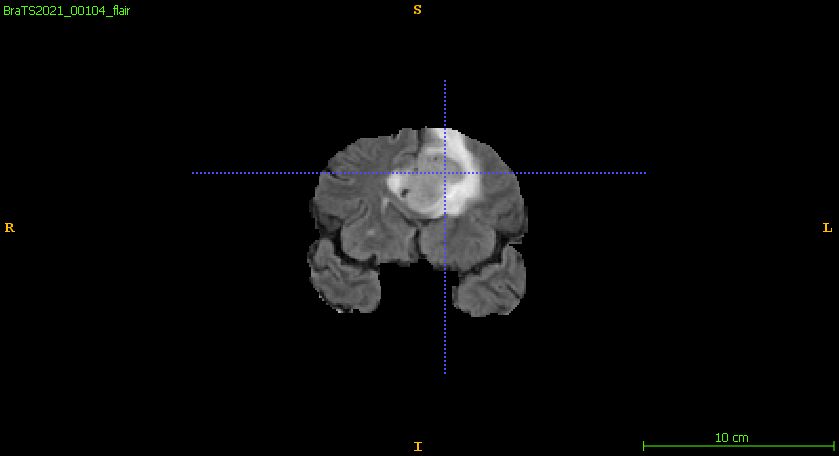

Furthermore, Figure 6 compares the ground truth on different planar views and the predicted segmentation labels corresponding to those views in the training set. The segmentation network demonstrates robust performance, accurately capturing the intricate details of tumor boundaries and structures across all planar views. The achieved DSC for the samples shown is 0.943 for ET, 0.957 for WT, and 0.949 for TC, reflecting the network’s high precision and reliability in segmenting different tumor regions. These results highlight the model’s effectiveness in generating segmentation outputs closely aligned with the ground truth.

Figure 6: Qualitative comparisons include (a–c) input FLAIR images with ground truth overlaid across axial, sagittal, and coronal views, (d–f) ground truth across the planar views, and (g–i) the corresponding predicted segmentation labels from the training set for each view.